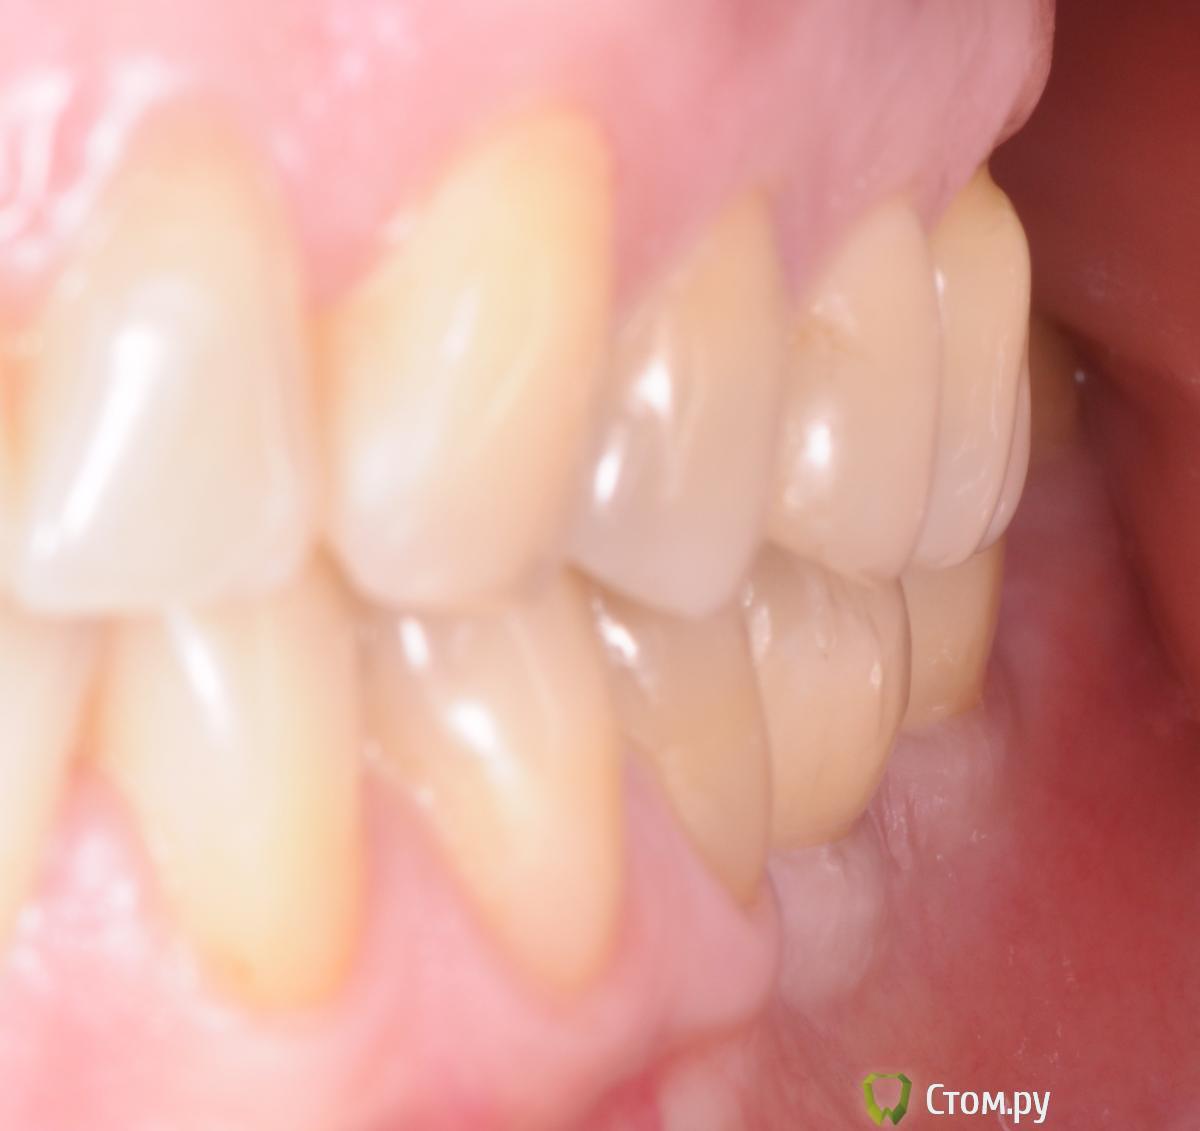

doctore Опубликовано 10 ноября, 2011 Поделиться Опубликовано 10 ноября, 2011 (изменено) ну эту картинку мы все видели ) хороший пример грамотных продаж ) Владислав, вы, как ментор Нобеля, наверняка сейчас активно начнете использовать новые имплантаты. Так вот, какая у вас будет форма абатмента на "нобель платформшифт" и "нобель ЦЦ" при установке Rp имплантата в дистальном отделе? Объем мягких тканей как раз таки легко создается десневой пластикой. Имплантолог,вероятно,крупно проигрался и задолжал.А тут две полные адентии откуда ни возьмись Согласен по поводу обьема и десневой пластики на 100%,но ведь в разумных пределах и при достаточной поддержке костной ткани(если она есть...Форма абатментов и результат,который я хочу видеть(это на Груви 4.3 и 5.0): Изменено 10 ноября, 2011 пользователем doctore Ссылка на комментарий

pit Опубликовано 11 ноября, 2011 Поделиться Опубликовано 11 ноября, 2011 (изменено) Имплантолог,вероятно,крупно проигрался и задолжал.А тут две полные адентии откуда ни возьмись Согласен по поводу обьема и десневой пластики на 100%,но ведь в разумных пределах и при достаточной поддержке костной ткани(если она есть...Форма абатментов и результат,который я хочу видеть(это на Груви 4.3 и 5.0): А Вы автор? И...... http://s42.radikal.ru/i096/1111/07/d9ba12a2a573.jpg Изменено 11 ноября, 2011 пользователем pit Ссылка на комментарий

doctore Опубликовано 11 ноября, 2011 Поделиться Опубликовано 11 ноября, 2011 (изменено) А Вы автор? И...... Пациентка одна-стороны разные.И хирургия и ортопедия мои. Изменено 11 ноября, 2011 пользователем doctore Ссылка на комментарий

pit Опубликовано 11 ноября, 2011 Поделиться Опубликовано 11 ноября, 2011 Пациентка одна-стороны разные.И хирургия и ортопедия мои.Очень даже симпатично. Исходные условия тоже хорошие. Десну формировали апикальным смещением и временными коронками?Нагрузили имплантаты одномоментно ли вторым этапом? В свете Ваших приципов идеализации лечения, этот кейс выглядит не завершенным, позвольте пульнуть камушек в Ваш огород))))))))))))))))))))))) Почему Вы не сделали интрузию 26 зуба и не установили имплант в позицию 27 зуба? ( спрашиваю как ортопед) А вобщем работа понравилась и врачебное, и техническое исполнение Ссылка на комментарий